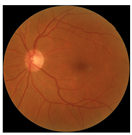

| No. | Fundus Image | Grad-CAM | Group | PRS | CNN | CNN+ML |

|---|---|---|---|---|---|---|

| 1 |  |  | Control | −1.07 | −0.57 | −1.95 |

| 2 |  |  | Control | −0.30 | −0.85 | −1.50 |

| 3 |  |  | Control | −3.12 | −1.53 | −1.83 |

| 4 |  |  | AMD | −0.99 | 0.29 | −0.86 |

| 5 |  |  | AMD | −0.23 | −0.29 | −0.66 |

| 6 |  |  | AMD | 0.17 | 1.31 | −0.75 |

| 7 |  |  | AMD | −0.43 | 1.16 | −0.48 |